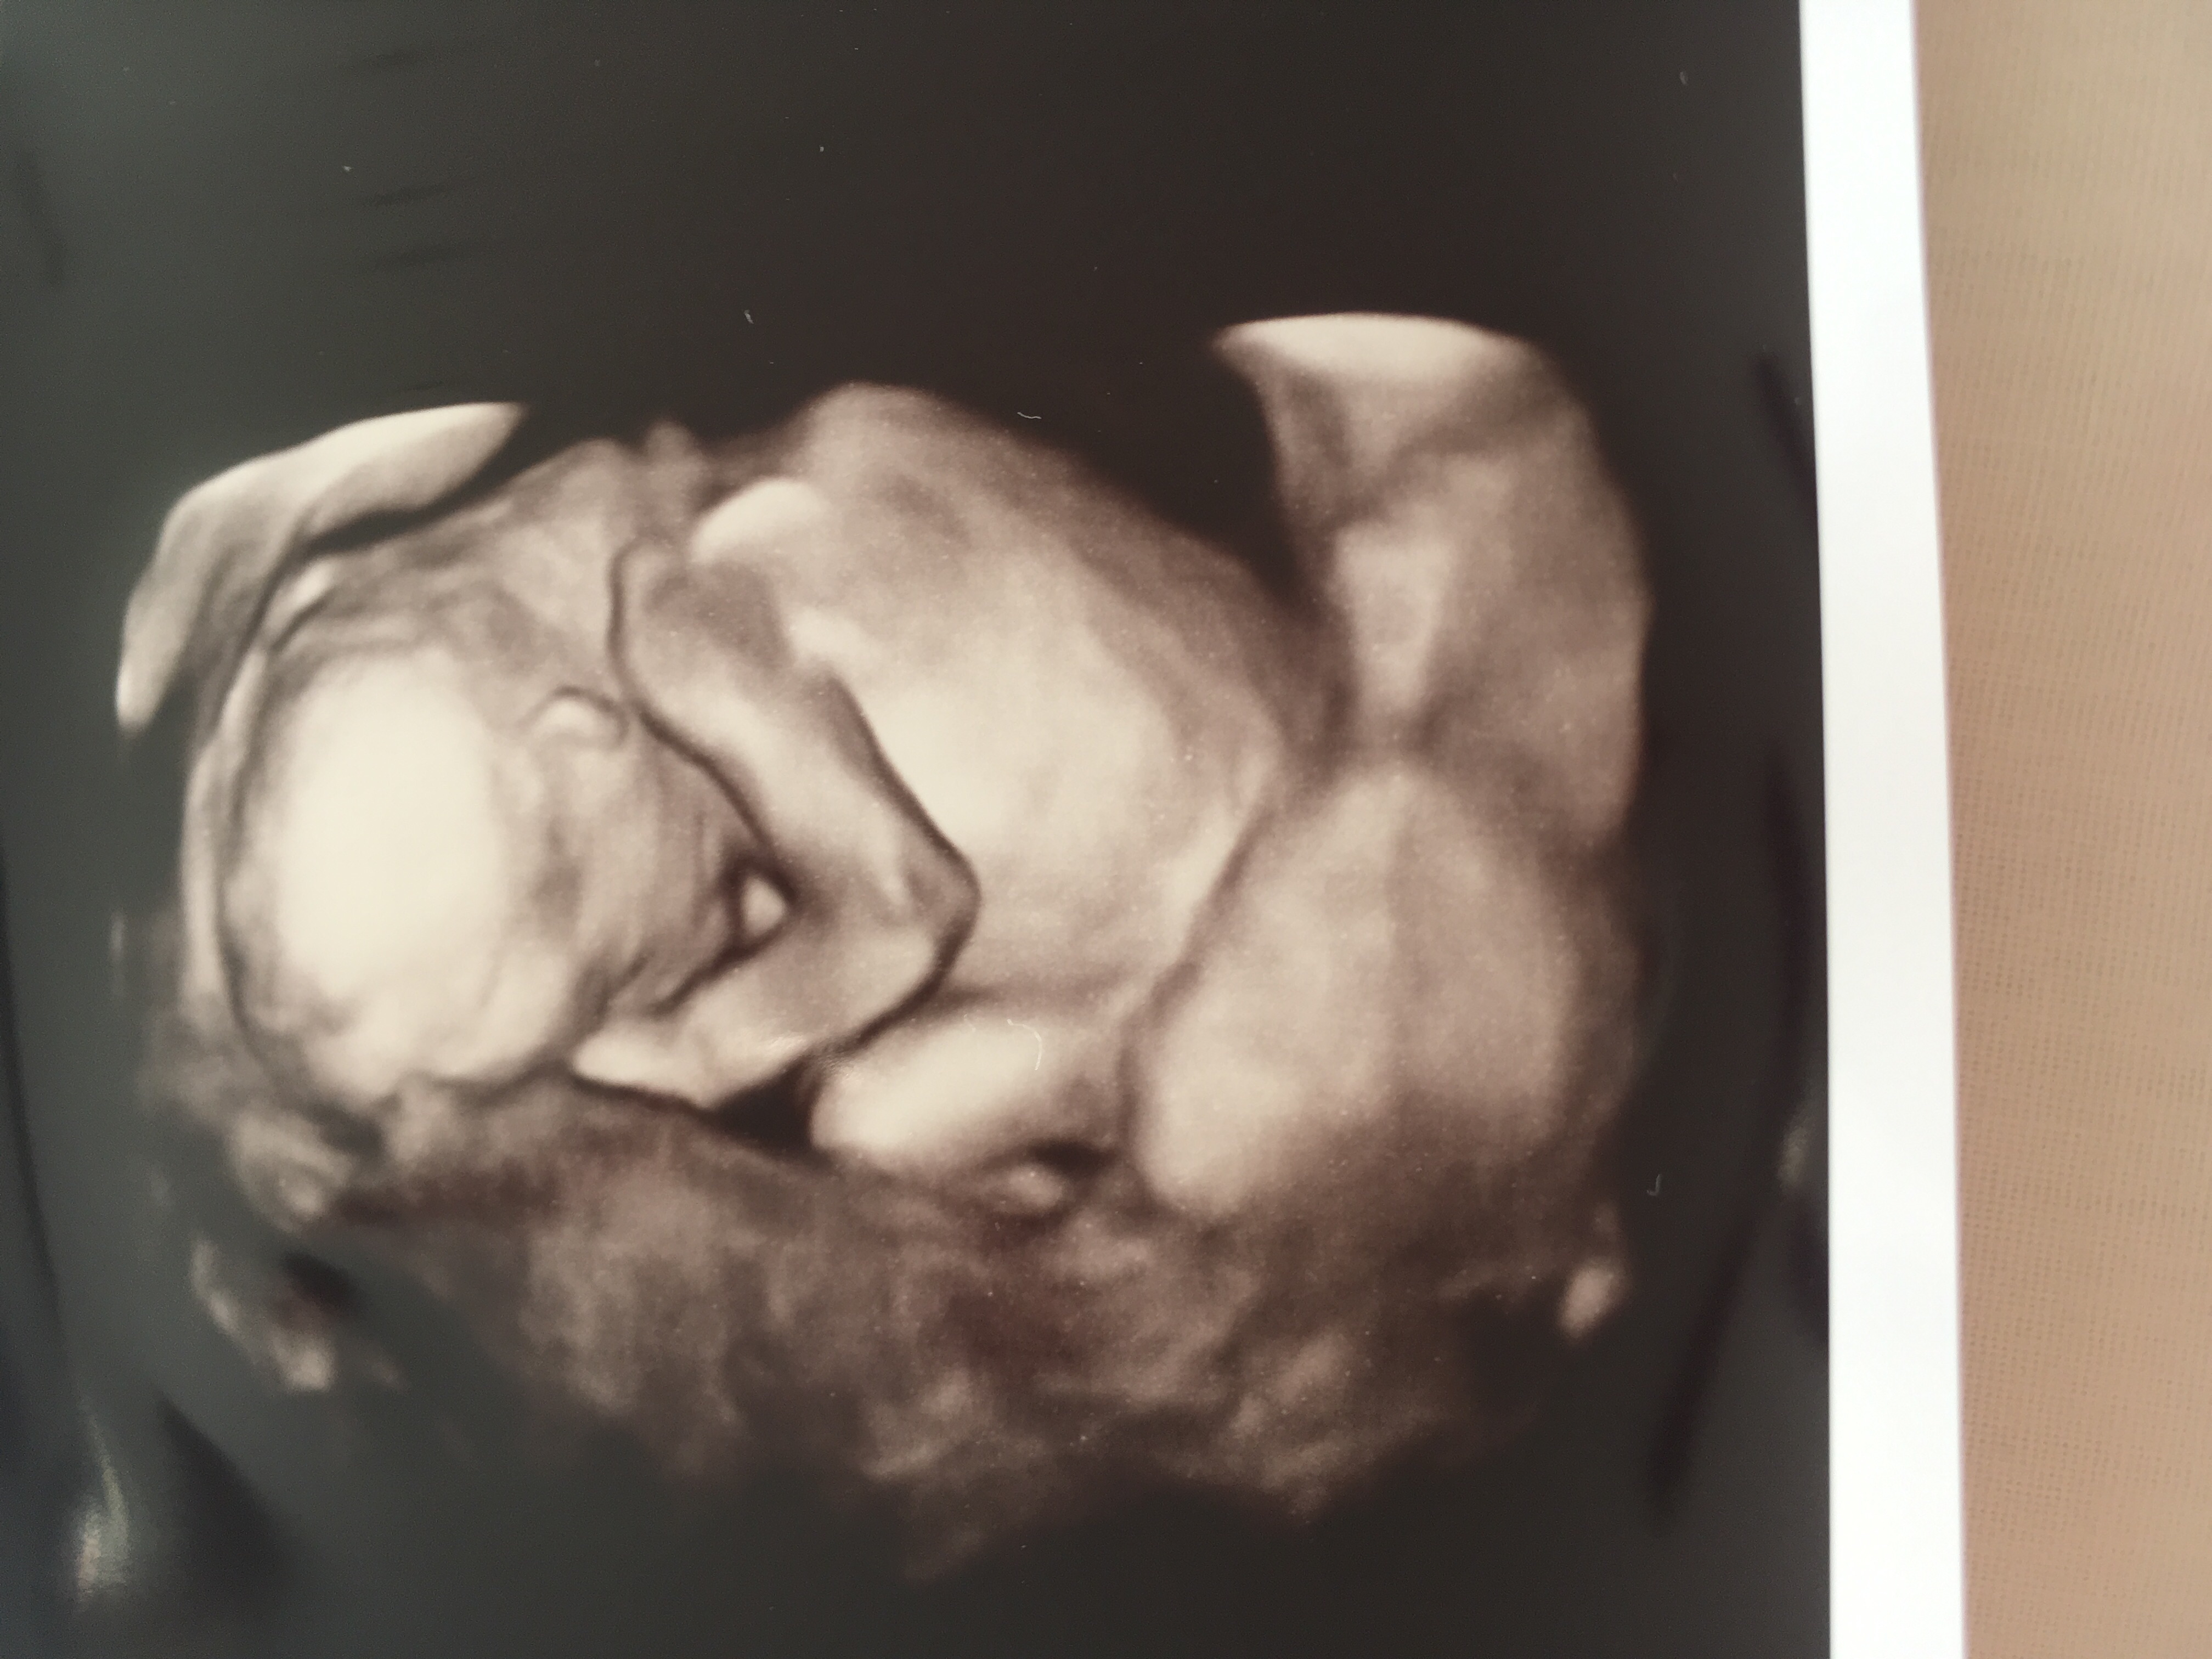

Had a private scan today looks boy tech was certain. Baby was not in great position and kept legs closed. Is there any way this isn’t a boy do you think?! Would it be very obvious now at nearly 17 weeks?

Hmmm. I guess you were hoping girl. I've done ultrasound and I have seen all my five boys. At that week if a tech says it, they are usually pretty sure. Mostly 15 weeks it gets accurate. It does look like a boy but if the tech was really unsure of the sex then I dont know. Let's hear what others say.

That does look like a boy. I'm sorry it's not what you were hoping for.

Yes, that looks boy to me. I'm so sorry it didn't go the way we hoped. But he is absolutely beautiful and I want to congratulate you on your new son. :heart: